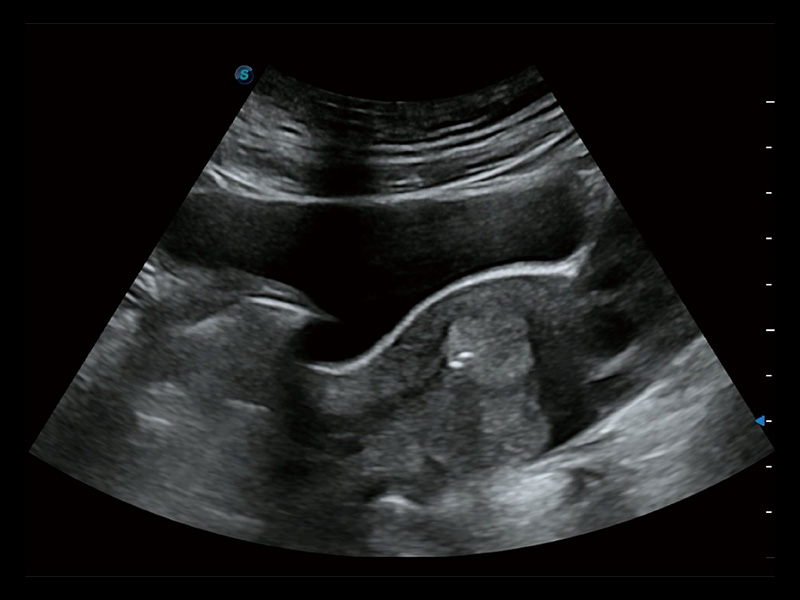

“生育问题”即关系民族复兴,也关系亿万家庭的幸福。随着婚育年龄推迟、社会压力增加等因素,越来越多人群也面临着“生不出、生不好”的问题。辅助生殖作为治疗不孕不育最有效的方法之一,也逐渐成为育儿新希望。而超声检查能为生殖需求人群的初诊评估提供宝贵的信息。 P20 Elite是球速体育入口匠心打造的一款生殖应用型彩超。她继承球速体育入口高端极光平台,突破性地将多款新型芯片及硬件模块进行整合,均衡了高端系统性能与小巧灵动机身。P20 Elite卓越的图像质量搭载专科探头,旨在为您提供全面的辅助生殖解决方案。

P20 Elite配备了丰富的生殖探头群和临床应用功能,在卵泡监测、穿刺取卵、胚胎移植、妊娠确认等领域,为生殖需求人群提供了新的临床机会,重新定义高端超声如何应用于生殖健康检查。